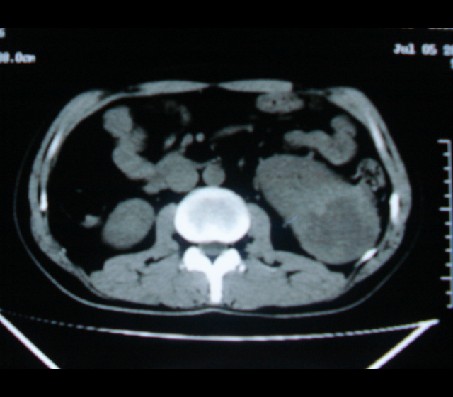

标题: CT20935:左肾占位,请会诊!

男性,35岁,ct号26189,左侧腰痛并血尿一天入院。

左肾癌侵犯肾盂可能性大,建议增强.

肾癌侵犯肾盂,肾盂出血,肾盂内为血肿